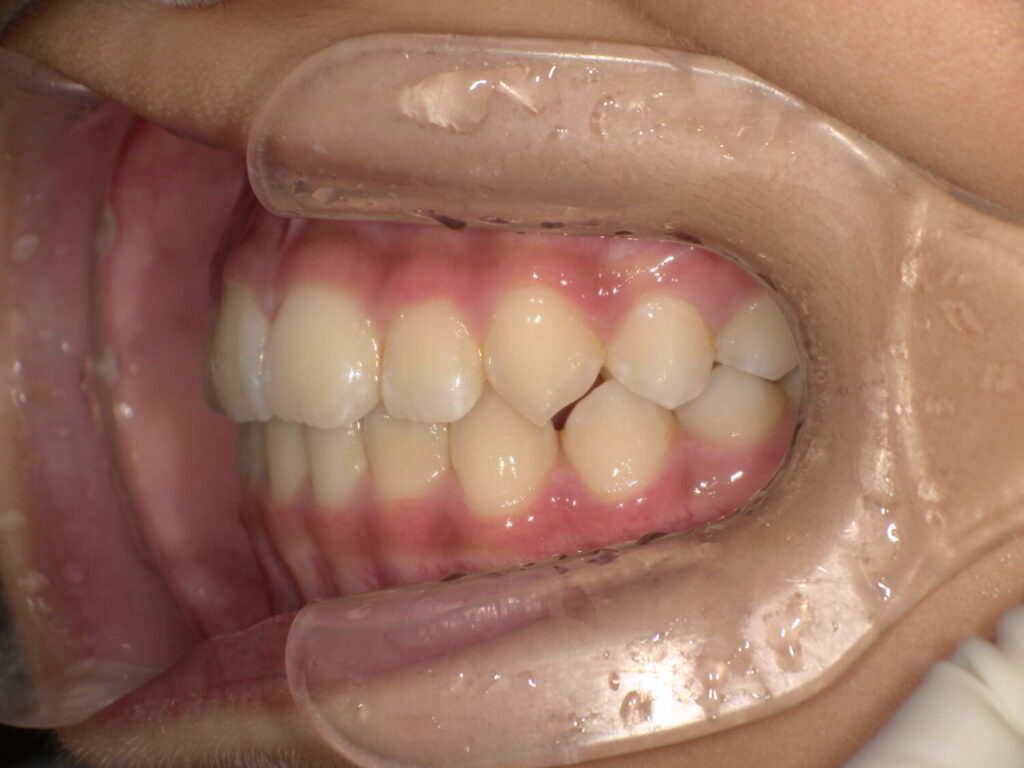

初めに撮った時の写真です。

上の歯と下の歯は噛んでいますが、歯と歯が先端でピッタリ噛んでいます。

最初の頃は上下の歯と歯がぴったりで噛んでいましたが、上の顎の写真の時と同じ日の噛み合わせ写真です。

まだ生えてる途中ですが以前より上下の差があります。

とても綺麗に噛み合っています!

いつも、鼻呼吸で舌をいい位置に置く、というのを続けてくれていると歯と歯もいい位置で噛んでいきます。